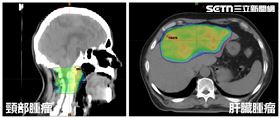

肝腫瘤如排球大!麻糬伯癌細胞壓頸害癱瘓

57歲麻糬伯曾罹患肝癌,經採用拴塞治療後效果頗佳,但...

2025/05/07 14:22